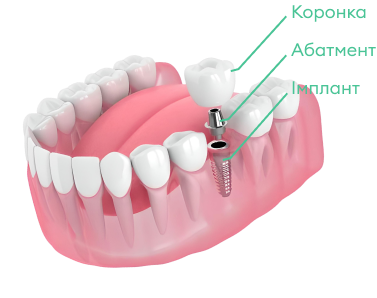

Безметалева коронка на імпланті.

Безметалева коронка на імпланті.

Це комплекс заходів щодо відновлення одного, декількох або всіх втрачених зубів методом встановлення імплантантів за фіксовану ціну.